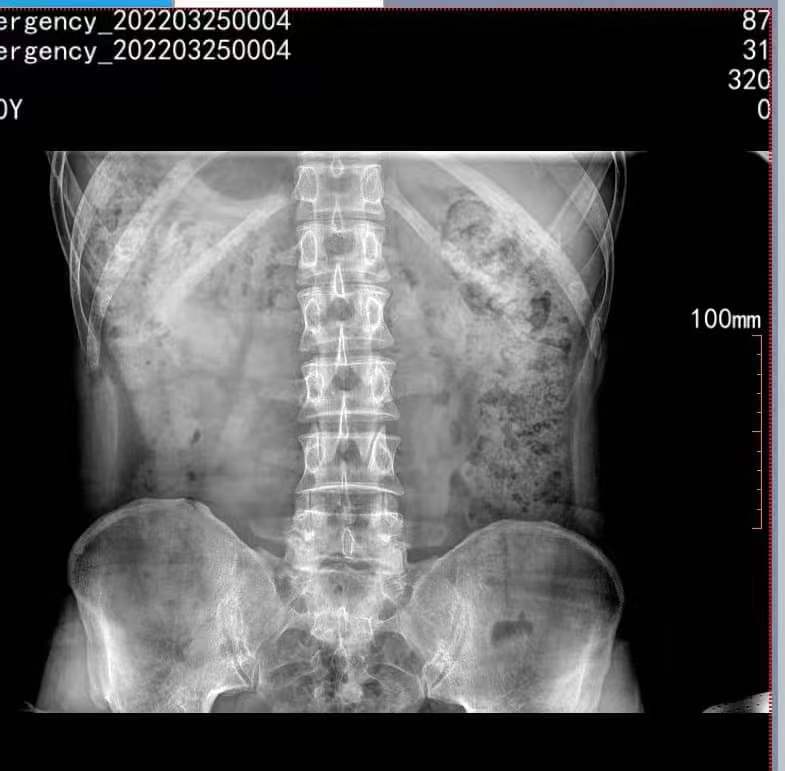

以下是拍摄腰椎正位的效果图:

X光机腰椎效果图